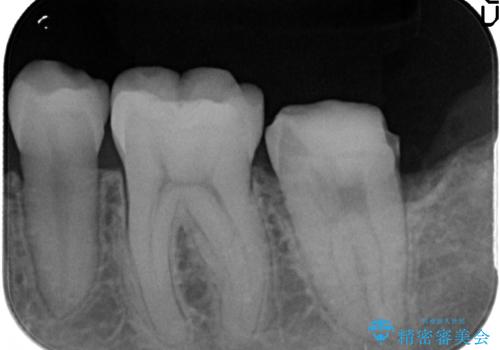

- 左下7の銀歯を白くしたいといらっしゃった方の症例です。

左下7遠心(下記のX線写真の左側)の歯質が歯肉縁下でかつポケットも深かったため、歯茎を下げる歯周外科を行いました。

その後歯茎の治りを待ちポケットが正常値であることを確認後、オールセラミッククラウンによる補綴を行いました。